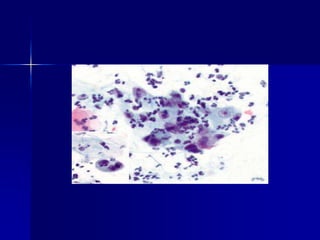

Marcadores tumorales en la identificación de neoplasias

indiferenciadas. Metástasis de melanoma en colon.

Marcadores tumorales enla identificación de neoplasias indiferenciadas. Metástasis de melanoma en colon.